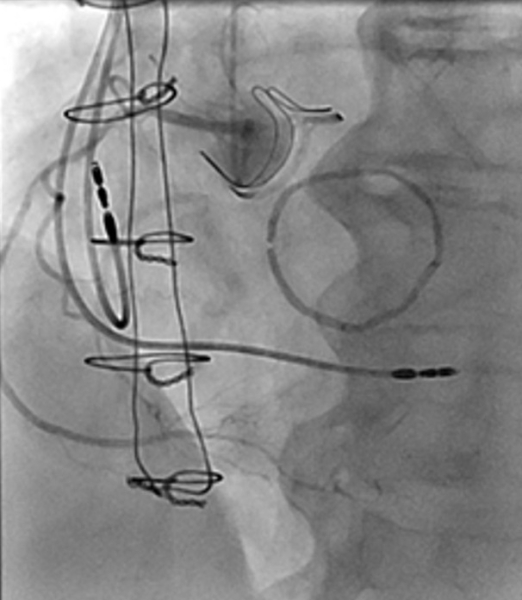

Nouvelle évaluation globale : cathétérisme

- POD : 13 mmHg

- PA 167/70 (100) mmHg

- PAPs 70 mmHg, PAPm 42 mmHg, PAPd 20 mmHg

- Pcap 28 mmHg

- Débit 5,13 L/min

- Index 2,9 L/min/m2

- RVP 2,73 UW

- Stent Circonflexe perméable

- Sténose significative de l’ostium de la bissectrice (traitement médical)

Figure 1